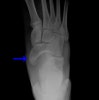

X-ray에서 발견하지 쉽지 않아 종종 놓치기도 합니다.

Oblique 45' view는 tuberosity fractures를 발견하기 유용합니다.

X-ray : 주상골 골절(Dorsal avulsion fracture)